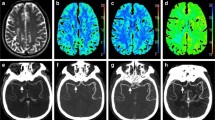

Further post-processing and quantitative VOI analysis

Quantitative/semi-quantitative parametric perfusion maps for the two techniques were further post-processed using the FMRIB software library (FSL) tools [16]. Brain extraction tool (BET) was used to delete the non-brain tissues from the images of interest [17]. Linear registration of the C-arm PBV maps and the MR perfusion parametric maps (CBF, CBV and MTT) for each patient was performed to the T1-weighted average structural template brain volume in the MNI152 space with FMRIB linear image registration tool (FLIRT) [18]. Binarized predefined cortical and subcortical volumes of interest (VOIs), as defined in the Harvard-Oxford structural brain atlas, were applied to the co-registered parametric maps. The 56 VOIs used for each hemisphere are depicted in Fig. 1. Mean, median and standard deviation values of each parameter were extracted for all VOIs encompassing both hemispheres. Given the semi-quantitative nature of MR-PWI measurements, we decided to use the interhemispheric ratios of all parameters for comparison. The interhemispheric ratios for MR-CBF, MR-CBV and C-arm CT PBV were calculated (e.g. right PBV/left PBV = relative PBV or rPBV) using a voxel-wise approach and the resulting relative parametric measurements, i.e. MR-rCBV, MR-rCBF and C-arm CT rPBV (prefix r = relative), were used for the subsequent statistical analysis. Figure 2 provides an overview of these image post-processing steps. For qualitative image analysis, two readers (an experienced neuroradiologist and a trained researcher) interpreted the parametric colour-coded perfusion maps for MR-PWI and C-arm CT PBV in a blinded fashion. A consensus interpretation of the colour-coded maps was used to define the perfusion abnormalities.

Harvard-Oxford structural brain atlas-based VOIs. Colour-coded illustration depicting the Harvard-Oxford structural brain atlas-based 3D VOIs of cortical and subcortical structures encompassing the whole brain, which were used for image analysis. Binarized masks of the 3D VOIs in orthogonal planes are shown. These binarized masks were used for extracting perfusion parameter values for various brain structures, which were subsequently used in the statistical analysis

A schematic overview of the image post-processing. a C-arm CT PBV dataset before brain extraction; b PBV dataset following brain extraction using FSL BET utility; c PBV dataset following threshold-based segmentation of the vascular structures; d registration of the PBV volume to the T1-weighted average structural template brain volume in MNI152 space; e brain-extracted, co-registered, vessel-segmented PBV volume in MNI152 space; f T1-weighted average structural template brain volume in MNI152 space to which the C-arm CT PBV maps and the MR-PWI data were co-registered; g binarized 3D-VOIs of cortical and subcortical structures encompassing the whole brain; h dynamic T2* weighted MR-PWI dataset; i registration of the MR-PWI to T1-weighted average structural template brain volume in MNI152 space; j registered MR-PWI dataset which was subsequently post-processed to extract perfusion parametric maps preserving the spatial coordinates in MNI152 space; k motion-corrected, vessel-segmented, brain-extracted, leakage-corrected, registered MR-PWI maps. Subsequently, using the binarized 3D-VOIs, the perfusion parametric values were obtained for the cortical and subcortical structures, which were then used in the statistical analysis

Fig. 6 Illustrative case example 1. A 50-year-old-woman with ruptured anterior communicating artery aneurysm developing left hemiparesis on day 6 post-SAH: Catheter angiogram images (a, b) show intense vasospasm affecting both ACAs (right > left) with corresponding abnormality (restricted diffusion) on MR-DWI image indicating established infarcts in the same territory (c). C-arm CT PBV (d), MR-PWI rMTT (e) and MR-PWI rCBV (f) images show asymmetric parametric deficits in the same distribution

Fig. 7 Illustrative case example 2. A 52-year-old-woman with ruptured basilar artery termination aneurysm a pre-treatment and e post-treatment catheter angiogram images show coil embolization and complete angiographic occlusion of the basilar artery termination aneurysm; b NCCT performed after the development of neurological deficits (day 4) excludes rebleed, hydrocephalus or infarction; c, d coronal and axial sections of C-arm FDCT PBV maps (day 6) show reduced PBV in both frontal lobes and in the left parietal lobe and f–h MR-PWI CBF, MTT and CBV maps (day 6) confirming a similar distribution of reduced perfusion in both frontal lobes and in the left parietal lobe